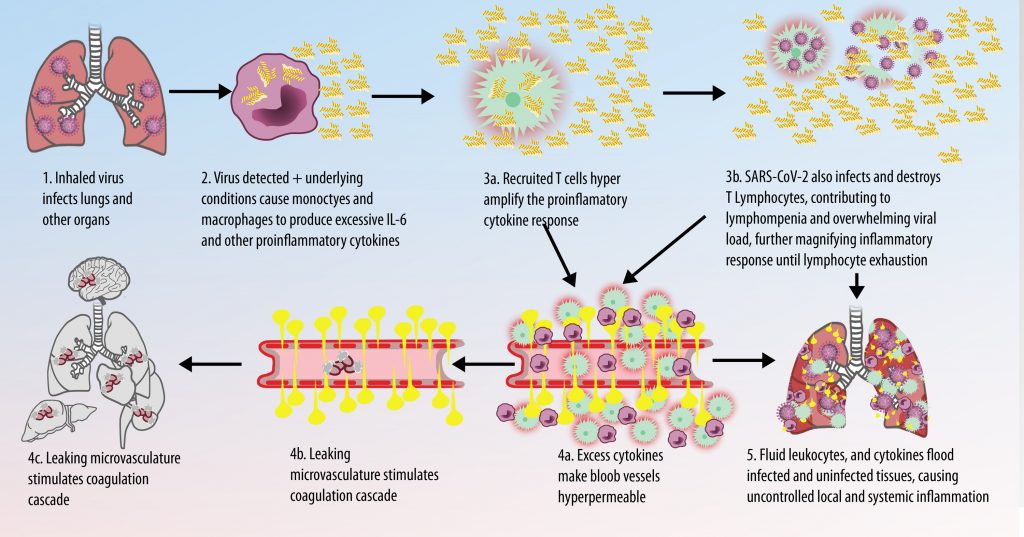

The vast majority of patients with COVID-19 have had a good prognosis, but there are still some critical individuals and even death.10 Most of these critically ill and dead patients do not develop severe clinical manifestations in the early stages of the disease. Some patients only show mild fever, cough, or muscle soreness. These conditions suddenly deteriorate in the later stages of the disease or in the recovery process . Acute respiratory distress syndrome (ARDS) and multiple-organ failure occur rapidly, resulting in death within a short time. Cytokine storm is considered to be one of the major causes of ARDS and multiple organ failure.

Cytokine Storm Syndrome (CSS) is characterized by systemic symptoms and signs derived from a massive and uncontrolled inflammatory response caused by pro- and anti-inflammatory cytokine dysregulation. Viruses, such as Herpes and Epstein-Barr are known to trigger CSS, as is H5N1 influenza. Current literature indicates that SARS-CoV-2 triggers CSS and has been attributed to the severe symptoms’ characteristic of critical patients. CSS in these patients is often fatal, as was the case in the previous SARS and MERS outbreaks.

The first cytokines released are interleukin 1β (IL-1β) and tumor necrosis factor-α (TNF-α), which attract a variety of circulating white blood cells (WBCs) to the infection site, including neutrophils, monocytes, macrophages, and natural killer (NK) cells. This response, along with the antipathogenic chemicals released by these cells (i.e., complement), comprise the innate immune response. These cells directly attack the invading pathogen and also release additional cytokines, chief among them interleukin-1 and 6 (IL-6). IL-6 is essential for invoking the adaptive immune response, which calls T-cells, B-cells, and T helper (Th) cells to the infection site. IL-6 also stimulates further recruitment, proliferation and activation of macrophages.

It is the ICU physician who is most likely to witness one of the deadliest manifestations of the abnormal immunological response, the cytokine storm syndrome (CSS). This response is also referred to by some as the cytokine release syndrome (CRS). CSS is characterized by continuous activation and expansion of macrophage and lymphocyte populations, which secrete large amounts of cytokines, causing the cytokine storm. This massive cytokine release is akin to hemophagocytic lymphohistiocytosis (HLH) disease, a syndrome characterized by initial unchecked and persistent activation of cytotoxic T lymphocytes and NK cells.

This activation induces inflammatory monocytes to highly express IL-6, starting a localized and then systemic cascade effect that results in hyperproduction of IL-6, which accelerates the inflammatory process. Because IL-6 also increases vascular permeability, excessive levels cause blood vessels to become very leaky. This, along with clotting factors released from vascular endothelial cells, stimulates the coagulation cascade, resulting in microthrombosis (tiny clots), which leads to ischemia and tissue death of the kidney, intestines, heart, liver, brain and extremities.